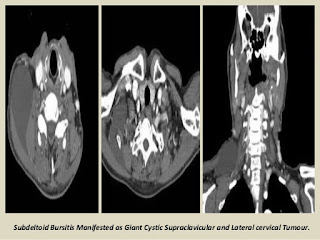

Bursa of shoulder.